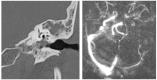

Background: This study presents a comprehensive analysis of cholesteatoma of the middle ear, focusing on its clinical presentation, diagnostic imaging, and treatment outcomes. Cholesteatomas are defined by the keratinized squamous epithelium within the middle ear, leading to significant bone erosion, often affecting the ossicular chain and surrounding structures. Methods: The study explores various mechanisms involved in cholesteatoma progression, including enzymatic lysis, inflammatory responses, and neurotrophic disturbances. The study conducted a retrospective clinical and statistical review of 580 patients over a 20-year period (2003-2023), highlighting the role of advanced imaging, including computed tomography (CT) and diffusion-weighted magnetic resonance imaging (DWI), in preoperative planning and postoperative follow-up. Results: Findings revealed that early detection and intervention are crucial in preventing severe complications such as intracranial infection and hearing loss. Surgical treatment primarily involved tympanoplasty and mastoidectomy, with a recurrence rate of 1.55% within two years. The study underscores the importance of integrating imaging advancements into clinical decision-making to enhance patient outcomes and suggests further investigation into molecular mechanisms underlying cholesteatoma progression and recurrence. Histopathological and microbiological analysis was performed to identify pathological patterns and microbial agents. Conclusions: The study highlights the importance of early diagnosis and intervention to prevent complications such as intracranial infections and permanent hearing loss, while also emphasizing the role of advanced imaging techniques in the management and long-term monitoring of cholesteatoma patients.